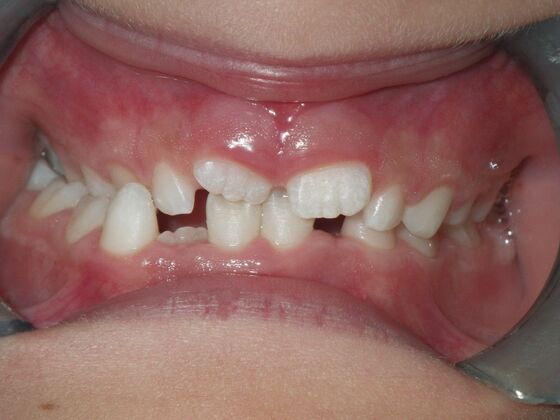

Orthodontic treatment in Phases: Case 8

Description

Dylan presented with a functional crossbite in which we used removable expansion appliances for 12 months, followed by bracketing of upper and lower teeth including primary ones to gain alittle more expansion, allowed to wear retainers for 6 months and then followed closely with 6 month ortho recalls and began Phase 2 treatment within 24 months and finished his ortho treatment.